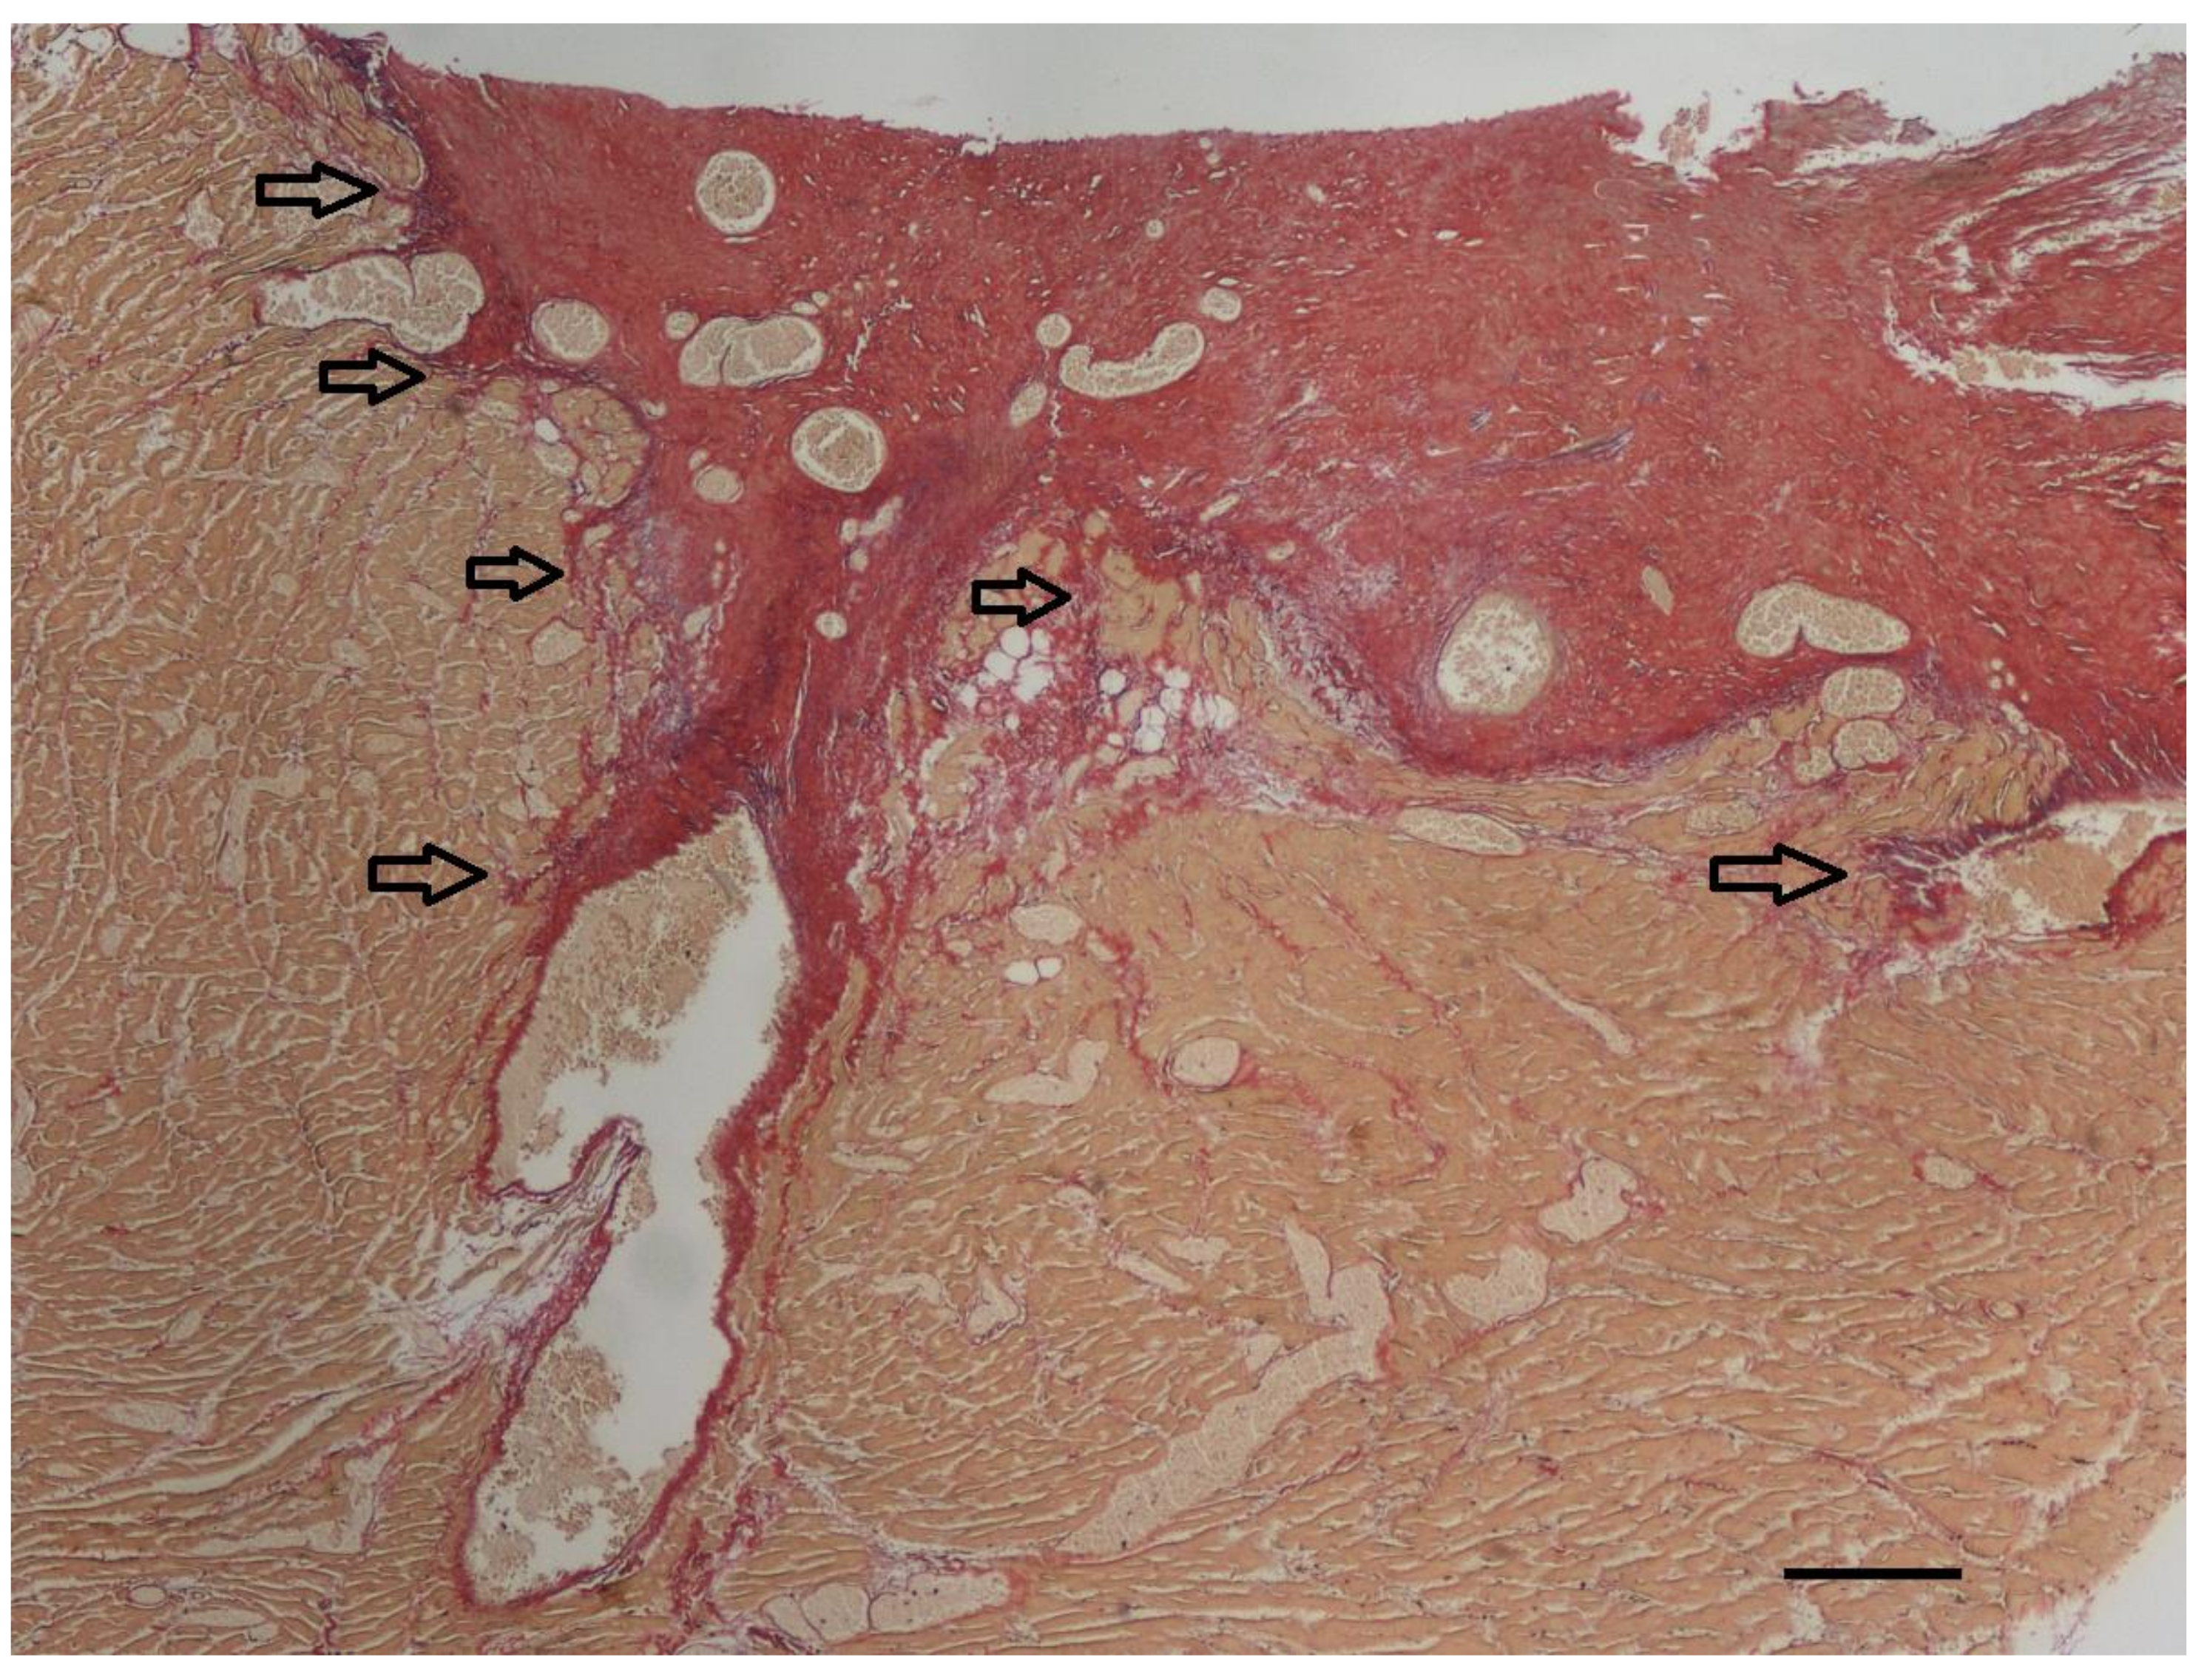

Histopathologic examination was performed on representative sites of the heart. The localized right ventricular muscular hypertrophy was composed of whirly arranged cardiomyocytes (Figure 7). Modified picrosirius red stain revealed severe focal endocardial fibrosis at the muscle bundle infiltrating the underlying right ventricular myocardium (Figure 8). The endocardium, myocardium, and pericardium, as well as the great vessels, were normal. The pulmonary alveolar septae showed mild fibrosis but no hemosiderin-loaded macrophages.

Figure 8. At the endocardial side of the longitudinal section of the right ventricular muscular hypertrophy (yellow), severe focal endocardial fibrosis (red) is present. The arrows indicate infiltration of collagen into the underlying myocardium. In addition to the thick subendocardial layer of collagen, collagen also surrounds the diffuse myocardial bundles throughout the underlying myocardium. Only a minimal increase in elastin fibers (violet) can be appreciated in this specimen accompanying the collagen fibers (red). Modified picrosirius red stain, bar = 200 µm.